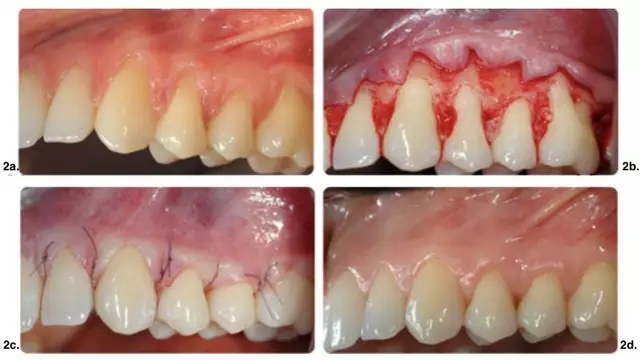

皮瓣設計無垂直切口治療多顆牙牙齦萎縮。實驗組手術及術后效果如圖 1 所示,CTG(涉及至少 2 個相鄰牙的牙齦萎縮)應用在有張力區(qū)域。對照組僅使用 CAF(圖 2)。

圖 2. 單獨應用 CAF 手術示意圖。